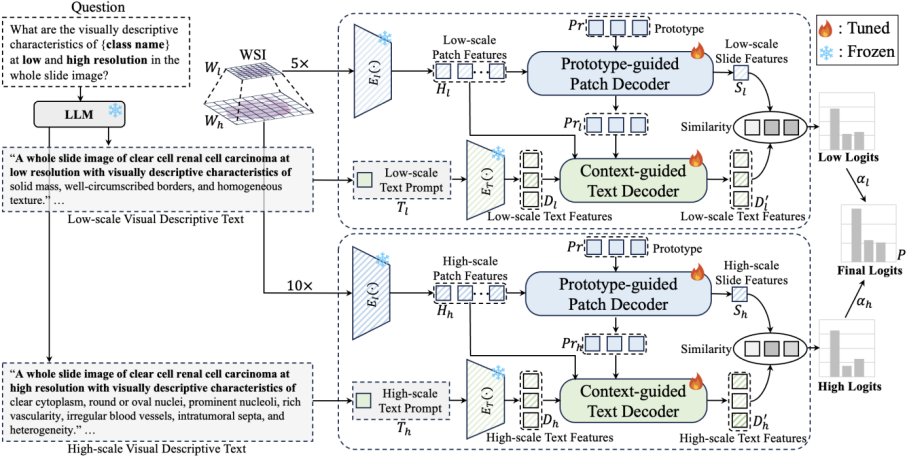

18

全病理图像的癌症亚型分类

ViLa-MIL: Dual-scale Vision-Language Multiple Instance Learning for Whole Slide Image Classification

Jiangbo Shi (Xi'an Jiaotong University), Chen Li (Xi'an Jiaotong University), Tieliang Gong (Xi'an Jiaotong University), Yefeng Zheng, Huazhu Fu (A*STAR of Singapore)

基于多实例学习(Multiple Instance Learning, MIL)的框架已经成为处理数字病理学中具有千兆像素大小和层次化图像上下文的全幅图像(Whole Slide Image, WSI)的主流方法。然而,这些方法严重依赖于大量的包级别标签,并且仅从原始图片中学习,这很容易受到数据分布变化的影响。最近,基于视觉语言模型(Vision Language Model, VLM)的方法通过在大规模病理图像-文本对上进行预训练,引入语言先验。然而,之前的文本提示(Text Prompt)缺乏对病理先验知识的考虑,因此并未实质性地提升模型的性能。此外,这种图文对的收集和预训练过程非常耗时,消耗大量算力资源。为了解决上述问题,我们提出了一个双尺度视觉-语言多实例学习(ViLa-MIL)框架,用于全幅病理图像分类。具体来说,我们提出了一个基于冻结的大型语言模型(Large Language Model, LLM)的双尺度视觉描述性文本提示,以有效地提升VLM的性能。为了让VLM有效地处理WSI,对于图像分支,我们提出了一个原型(prototype)引导的图像块(patch)解码器,通过将相似的图像块分组到同一原型中,逐步聚合图像块特征;对于文本分支,我们引入了一个上下文引导的文本解码器,通过整合多粒度图像上下文来增强文本特征。在三个多癌种、多中心癌症亚型分类数据集上的广泛研究证明了ViLa-MIL的优越性。